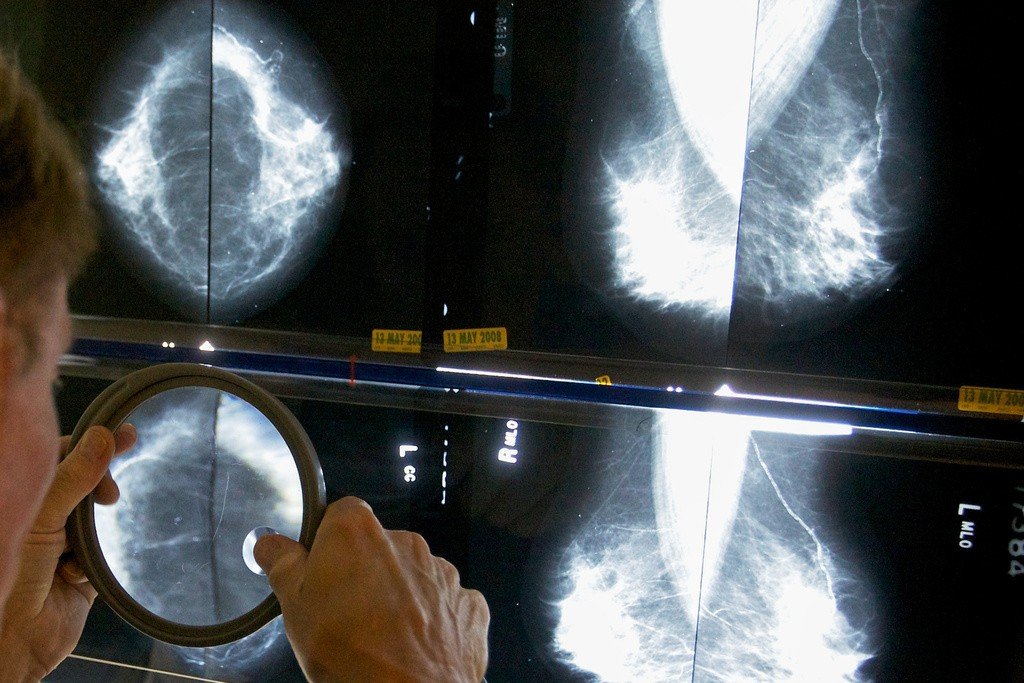

Radiologista usa lupa para examinar mamografias em busca de câncer de mama.

AP/Damian Dovarganes/Arquivo